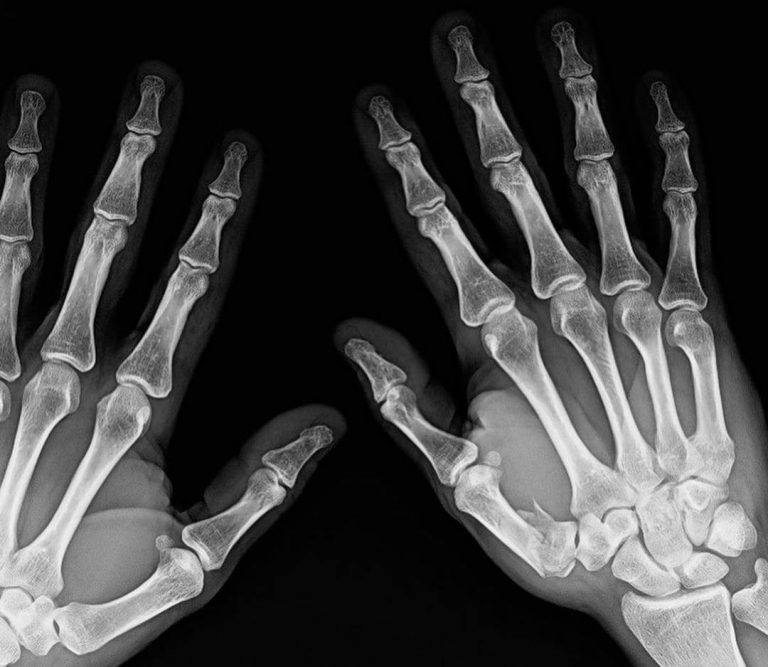

Joaquim Rodríguez (1979) sufre la fractura de tres dedos después de la aparatosa caída que sufrió el miércoles en Andorra, cuando practicaba descenso en la montaña, y será operado de las dos manos.

Purito ya se encuentra en Barcelona donde le han diagnosticado dos dedos rotos en la mano derecha y uno en la izquierda, tras pasar revisión en el Institut Català de Traumatologia i Medicina de l’Esport (ICATME) con el traumatólogo Xavier Mir. El exprofesional retirado en 2016 será operado en breve.

«En dos manos tres huesos rotos y un montón de contusiones. El martes me opera el jefe Mir las dos manos, así que se me hará difícil contestar a todos los que os habéis interesado por mi. Os agradezco los ánimos a todos los que me habéis escrito wattsapp, insta,etc… pero como veis no os puedo responder… un millón de gracias! En cuanto me recupere le vuelvo a pegar al mismo salto!!!!